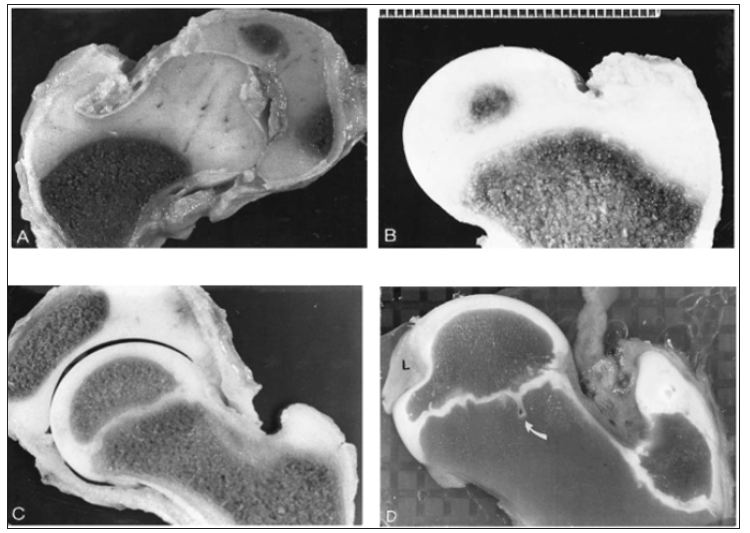

The acetabular ring epiphysis which surrounds the acetabular margin contributes nearly 30% to acetabular depth. Small centers of ossification appear in the ring epiphysis between 11 and 14 years. It usually fuses to the acetabular margin in mid-adolescence. The triradiate cartilage closes at about 11 years in girls and a year later in boys [2]. Development of the proximal femoral chondroosseous epiphysis and physis is probably the most complex of all the appendicular skeletal growth regions [3]. Figure 1 illustrates several stages in the development of the proximal femur. Perhaps the two most important features are (1) the continuity of epiphyseal and physeal cartilage along the posterosuperior neck throughout much of postnatal development and (2) the intracapsular course of the limited capital femoral blood vessels.

Figure 1: Slab sections showing proximal femoral development. (A) At 2 months a contiguous epiphysis encompasses the capital femur and greater trochanter. The intrinsic vascularity of the capital femoral cartilage is evident. (B) At 8 months the capital femoral ossification center is developing, and the femoral neck (metaphysis) is forming. (C) At 8 years undulations are developing in the capital femoral physis. (D) At 12 years there is a normal indentation of the ossification center at the site of attachment of the capital femoral ligament (L); the capital femoral physis is extensively undulated, and a mammillary process (arrow) is evident (Ogden JA, 1983).

Secondary ossification usually begins in the capital femur by 4-6 months postnatally (range 2-10 months). This process is a centrally located sphere of ossification that expands centrifugally, eventually conforming to the hemispheric shape of the articular surface by the time the child is 6-8 years old and forming a discrete subchondral plate that follows the capital femoral physeal contour [3]. Throughout most of the development the capital femoral and trochanteric epiphyses have a cartilaginous continuity along the posterior and superior portions of the femoral neck (Figure 2). Although this region gradually thins as the child grows, it is essential for the normal latitudinal growth of the femoral neck and, in part, the normal decrease in anteversion (Figure 2).

The development of the femoral neck brings about changes in the contour of the capital femoral physis. Initially, the femoral neck is transversely directed (Figure 1); but during the first year there is preferential growth in the medial, and middle sections. As these regions develop, the capital femoral physis becomes more medially (Varus) and posteriorly oriented, which eventually may predispose to slipped capital femoral epiphysis. Lappet formation, undulations, and mammillary processes develop in the physis (Figure 1), again becoming more evident after 10 years of age. These processes and contours serve to “anchor,” or stabilize, the capital femoral epiphysis to prevent displacement due to biologic shear stresses [3].